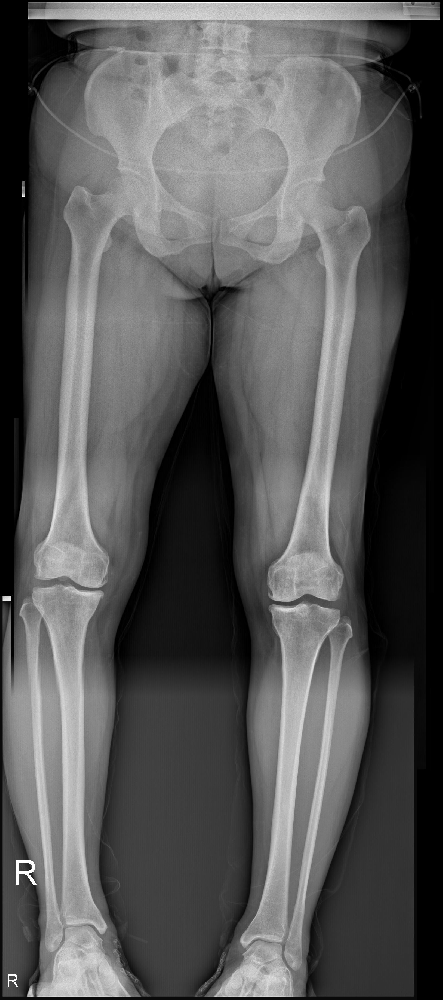

李煥云,51歲的女性,來自市中區(qū)永安鄉(xiāng)天西村。她帶著7年疼痛的右膝和2年疼痛的左膝走入市中區(qū)誠德骨科醫(yī)院。歲月的磨礪使她變得堅強,而疼痛卻成了她生活的沉重負擔。讓我們跟隨她的腳步,一同探索她心中的堅韌和勇氣。

患者自述,7年前,她在重勞累后首次感到左膝關(guān)節(jié)的疼痛,而這疼痛隨著時間的推移逐漸加重?;顒訒r,雙膝的疼痛伴隨著身體的每一個動作,蹲起更成了一種奢求。她曾在診所涂抹治療用的膏藥并口服藥物,疼痛的確得到了一定的緩解,但是在一段時間后,癥狀卻又復(fù)發(fā)了。

2年前,左膝的疼痛問題再次找上李煥云。這一次,疼痛是間斷發(fā)作的,特別是在勞累后更加明顯。只有休息,她才能夠暫時放下疼痛的包袱。不幸的是,1年前,她的雙膝同時加劇了疼痛的程度。疼痛達到了無法忍受的地步,以至于她不得不依賴口服止痛藥來緩解痛苦。

病情的加重使她決定前往市中區(qū)誠德骨科醫(yī)住院接受更全面的檢查。在這次住院期間,醫(yī)生進行了雙側(cè)脛骨高位截骨加接骨板螺釘內(nèi)固定手術(shù),而術(shù)后的康復(fù)進展令人欣喜。

圖片1.png